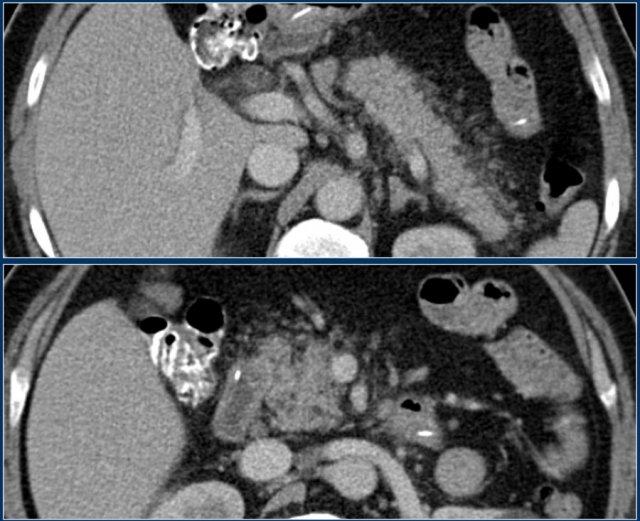

Các dấu hiệu bao gồm:

- Tụy ngấm thuốc bình thường toàn bộ.

- Các ổ dịch quanh tụy lan rộng, có tỷ trọng dạng lỏng và không lỏng trên CT.

- Có ít nhất hai ổ dịch, nhưng không có hoại tử nhu mô tụy (CTSI: 4).

- Vào ngày thứ 18, các ổ dịch quanh tụy mở rộng và xuất hiện thành không hoàn toàn.

Vào ngày thứ 5, ổ dịch này có thể được chẩn đoán là ổ hoại tử cấp tính có khả năng cao.

Vào ngày thứ 18, thành chưa hoàn toàn, nhưng có thể dự đoán rằng trong vài ngày tới đây sẽ trở thành ổ hoại tử được bao bọc với thành hoàn chỉnh.

Khi các ổ dịch quanh tụy tồn tại dai dẳng hoặc tăng kích thước, thường là do sự hiện diện của hoại tử mỡ.

Do mỡ không ngấm thuốc trên CT, việc chẩn đoán hoại tử mỡ có thể gặp khó khăn.